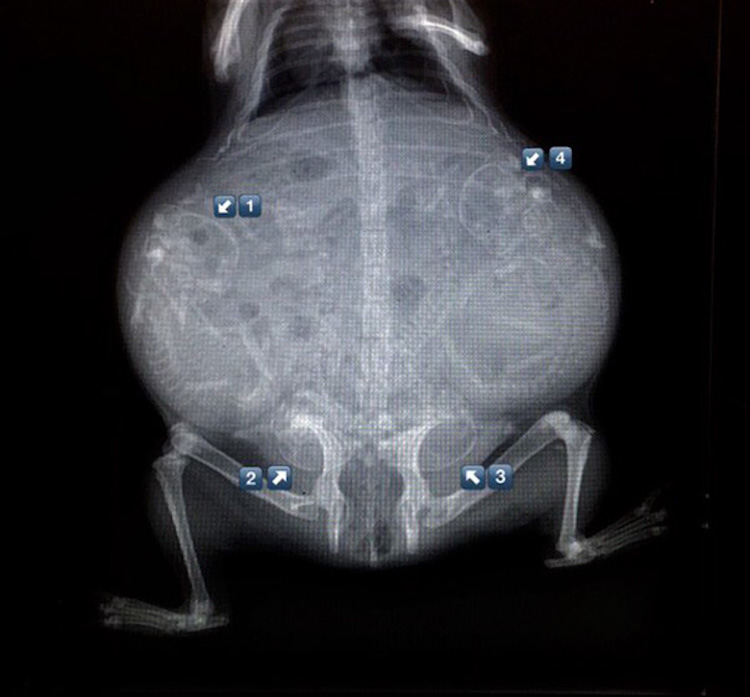

5 – Chienne enceinte. Comme les femmes, les chiennes sont enceintes pendant trois trimestres-chaque 21 jours de long. Autour de 45 jours, il est possible de déterminer au rayon-x combien de chiots feront partie de la portée.